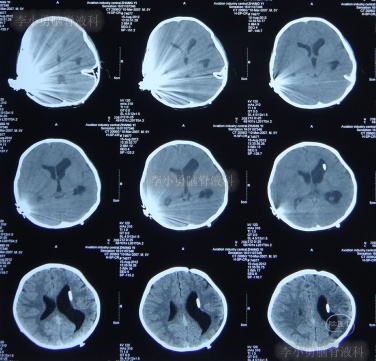

在利奈唑胺、头孢吡肟、利福平等药物抗炎治疗2周后,发热症状逐渐得到控制,意识也开始转清醒,但患儿自己示意有头痛症状;因腰穿未能抽出脑脊液,所以给予甘露醇处理,之后头痛可有缓解。在住院11天时即2012年5月27日(图-4)和住院14天时即2012年6月1日(图-5),分别进行过脑CT的检查,显示脑室有逐渐扩大的表现,但因为病情有所缓解,所以给以继续密切观察的处理。

图-4:2012年5月27日脑CT脑室稍扩大

图-5:2012年6月1日脑CT脑室稍扩大

但是在住院第19天即在2012年6月6日时(注:即在人工耳蜗植入术颅内感染并发症21天时),患儿出现了左眼闭合和右侧肢体瘫痪即交叉性偏瘫,以及进食无力和不能交流的病情加重的表现,立即脑CT检查发现了脑积水的表现(图-6)。

图-6:2012年6月6日脑CT脑室扩大显著